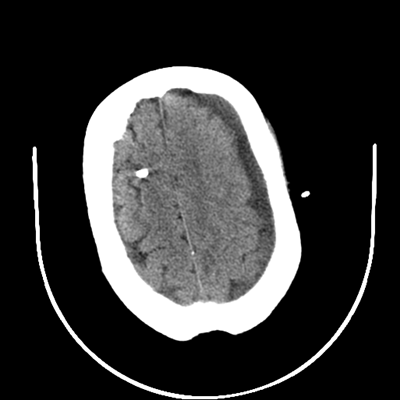

The patient goes down to CT. The following images are obtained. The subdural fluid collection is stable, as is the ventricular caliber.

Starting with the non-contrast head CT, we can appreciate that there's actually not much residual subarachnoid blood at all; it's essentially all resorbed already (and cleared through the EVD). The ventricular caliber is stable. With the CTA head (for convenience's sake, the MIPs were shown), it's subtle, but we can see that the PCAs on each side are not as smooth and regular. The right MCA, starting at the bifurcation, also becomes narrower. This is [radiographic] vasospasm. Now, looking at the CT perfusion-- specifically, the Tmax (MTT) map that were selected-- there's clearly some abnormality within the bilateral cerebellar hemispheres and occipital lobes. Not a lot, but it's there. Delving further into this map, we can appreciate that the areas of abnormality are mainly green, signifying that these areas have Tmax > 6 seconds. This is the threshold that is specific, not sensitive, for vasospasm.

Putting this all together, we have thus identified radiographic vasospasm with the vessel imaging, with perfusion abnormalities that are concordant with it. Does the area of vasospasm and hypoperfusion correlate with the patient's clinical exam?

Yes! It does. The patient had a decline in level of consciousness with diffuse loss of motor function. This does correlate to the basilar territory. (Alternatively, bilateral MCA vasospasm could also be responsible, reminding us that a decline in consciousness could technically be focal/multifocal.) Thus, we can say that this patient does have clinical vasospasm. Whether this will develop into irreversible DCI remains to be seen; at least, the non-contrast head CT and the other portions of the CT perfusion (not shown) currently don't [yet] suggest infarction.